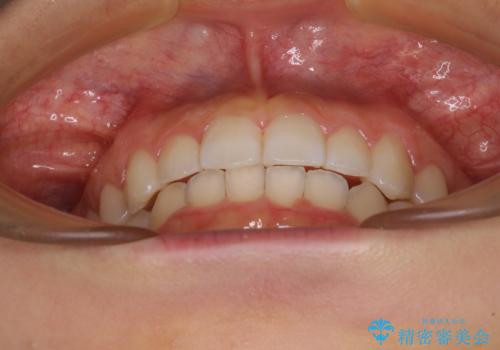

前歯のデコボコと突出感 インビザラインによる矯正治療

- 上下前歯のデコボコと、上顎前歯の突出感を気にして来院された患者様です。

インビザラインによる上下歯列の側方拡大と後方移動、IPR(歯と歯の間を削る)にるスペースの獲得により歯列を整えることとしました。

毎日22時間以上しっかりとマウスピースを装着していただいたので、スムーズに治療が進みました。歯と歯の間を削ることでうまくスペースコントロールでき、1年強で終えることができました。